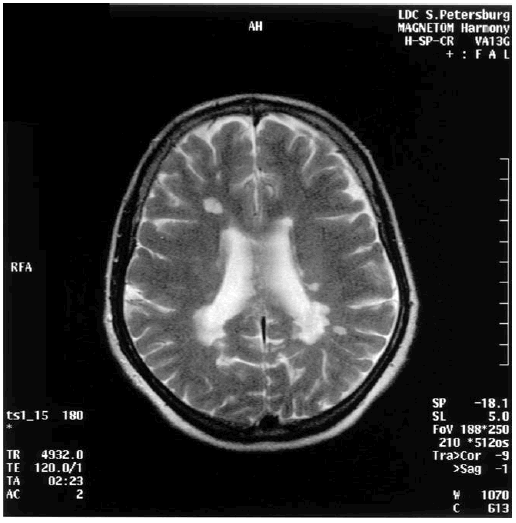

Выявленное сочетание нарушения внимания и памяти у таких больных, а также улучшение изученных показателей в ремиссию согласуются с результатами других исследователей [266]. Нарушения когнитивных функций, по данным МРТ головного мозга, у этих больных объясняют разрушением фронтопариетальных субкортикальных сетей. Показано частое вовлечение в патологический процесс мозолистого тела, что имеет большое значение в развитии нарушений когнитивных функций и поведения у больных с рассеянным склерозом. У обследованных больных улучшение психометрических показателей коррелировало с динамикой МРТ головного мозга: уменьшалось накопление парамагнетика гадолиния в участках демиелинизации, что является одним из морфологических критериев обратного развития очагов рассеянного склероза. На рис. 10.1 представлена МРТ головного мозга пациентки 46 лет (продолжительность болезни двенадцать лет) с рассеянным склерозом и картиной умеренной деменции.

Рис. 10.1. МРТ головного мозга пациентки с рассеянным склерозом и деменцией